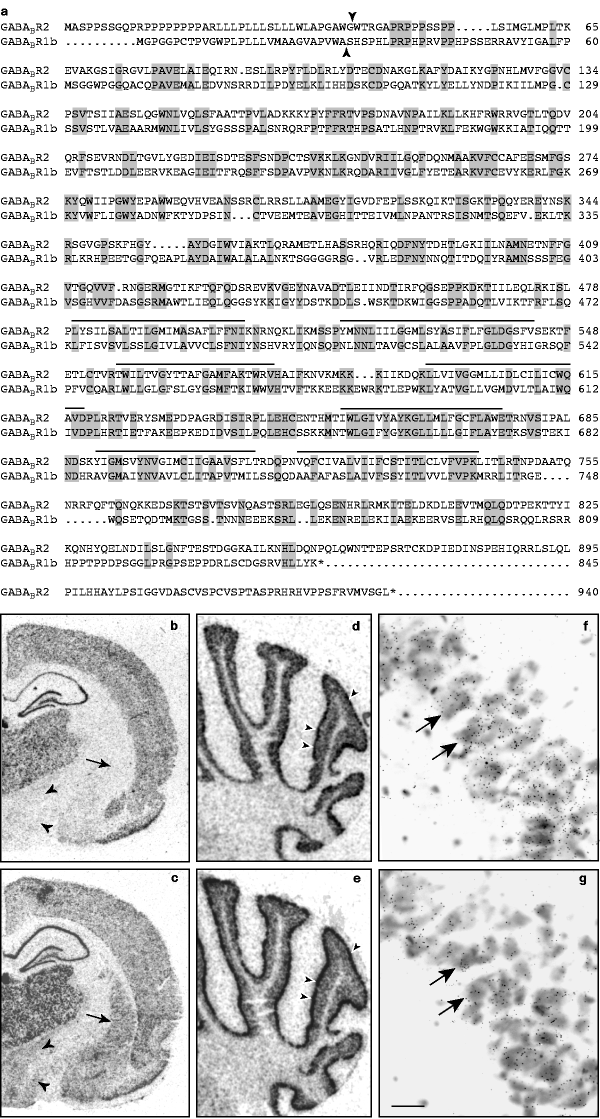

Gaba B Receptors Function As A Heteromeric Assembly Of The Subunits Gaba B R1 And Gaba B R2 Nature

Deficits In The Activity Of Presynaptic G Aminobutyric Acid Type B Receptors Contribute To Altered Neuronal Excitability In Fragile X Syndrome Journal Of Biological Chemistry